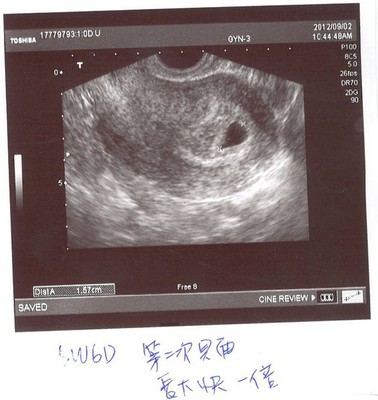

For my baby- 9/2驚慌 5W6D

5W6D.jpg 一早你老爸相當悠閒的說先吃完早餐再過去,媽媽的心情還算輕鬆, 由於你還小,所以這一次還是須要做陰道超音波,報到處的護士阿姨很溫柔,很堅持必須幫媽媽算預產期,但由於多多囊性...